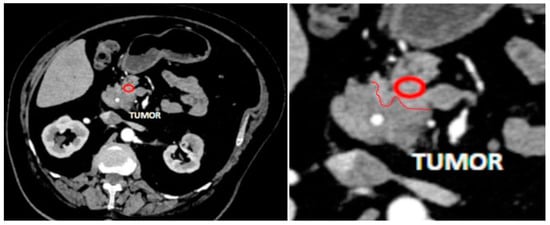

2.2. MDCT Examination

2.3. MDCT Result Post-Processing